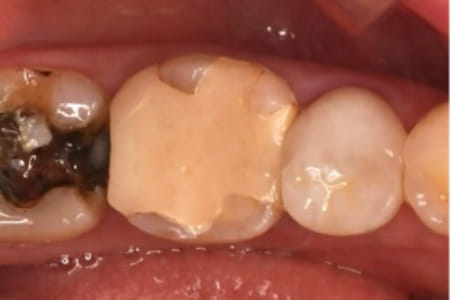

近所のかかりつけの歯科医院で、「再治療できないから奥歯を抜くしかない」と言われた。

あきらめきれず、HPで探して当院へ来院。

外すと中がドロドロに虫歯に感染していました。

折れて残っていた機具を除去